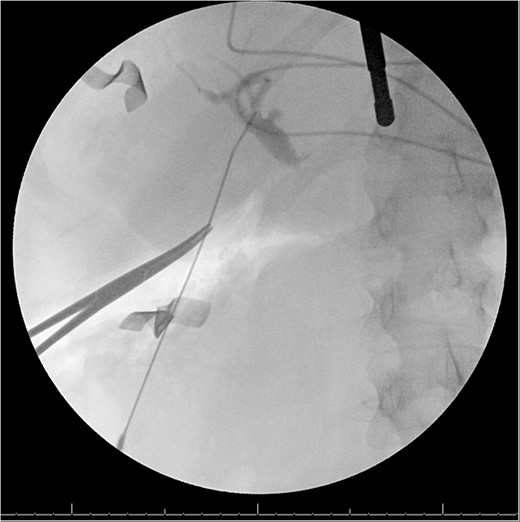

A 49-year-old female with a history of ADPKD and multiple liver cysts, 13-months status post subtotal cholecystectomy, endoscopic retrograde cholangiopancreatography with biliary sphincterotomy and balloon stone extraction, presented to the emergency department with fever and a 4-day history of discomfort in the right upper quadrant. At the time of the initial cholecystectomy, total cholecystectomy could not be performed due to extensive adhesions, and subtotal cholecystectomy with complete evacuation of the stones was done instead. Magnetic resonance cholangiopancreatography (MRCP) done at that time showed a dilated common bile duct (CBD) to 1.5 cm, intra and extrahepatic biliary dilatation, multiple liver cysts measuring up to 2 cm, and multiple stones in the CBD, including at the level of the ampulla (Fig. 1). Computerized tomography scan at the time of the second admission showed acute cholecystitis and she had mildly elevated transaminases, but there was no evidence of cholestasis or pancreatitis. MRCP showed minor proximal intrahepatic biliary dilation and cholelithiasis but no duct calculi (Figs 2–4). A laparoscopic cholecystectomy was attempted with extensive adhesiolysis between the gallbladder and surrounding omentum and mesocolon, but the cystic duct could not be isolated, and ultimately the cased was converted to open. While removing the gallbladder in a top-down fashion, a small bile leak was identified right at the closed end of the gallbladder remnant, where the bile duct was adhered to the gallbladder wall. Intraoperative cholangiogram was obtained through a small perforation in a right posterior bile duct at the site of attachment, which showed right posterior, right anterior and left hepatic ducts of equal size converged at a trifurcation (Fig. 5). The duct was repaired over a T-tube and observed throughout the rest of the case and no bile leak was identified. The gallbladder was opened along its lateral edge, revealing a hugely dilated cystic duct with ~10 to 12 marble-sized stones packed within the gallbladder remnant and cystic duct down to the juncture with the common bile duct. All the stones were removed and the safe portion of the gallbladder remnant was resected leaving the side attached to the bile duct in situ due to the Mirizzi anatomical variant. The cystic duct was oversewn along with the remnant of the gallbladder wall. Pathology showed acute-on-chronic cholecystitis with cholelithiasis. Repeat MRCP showed no retained stones in the biliary tree. The recovery course was unremarkable.

MRI/MRCP from second hospitalization demonstrating CBD of 1.1 cm.